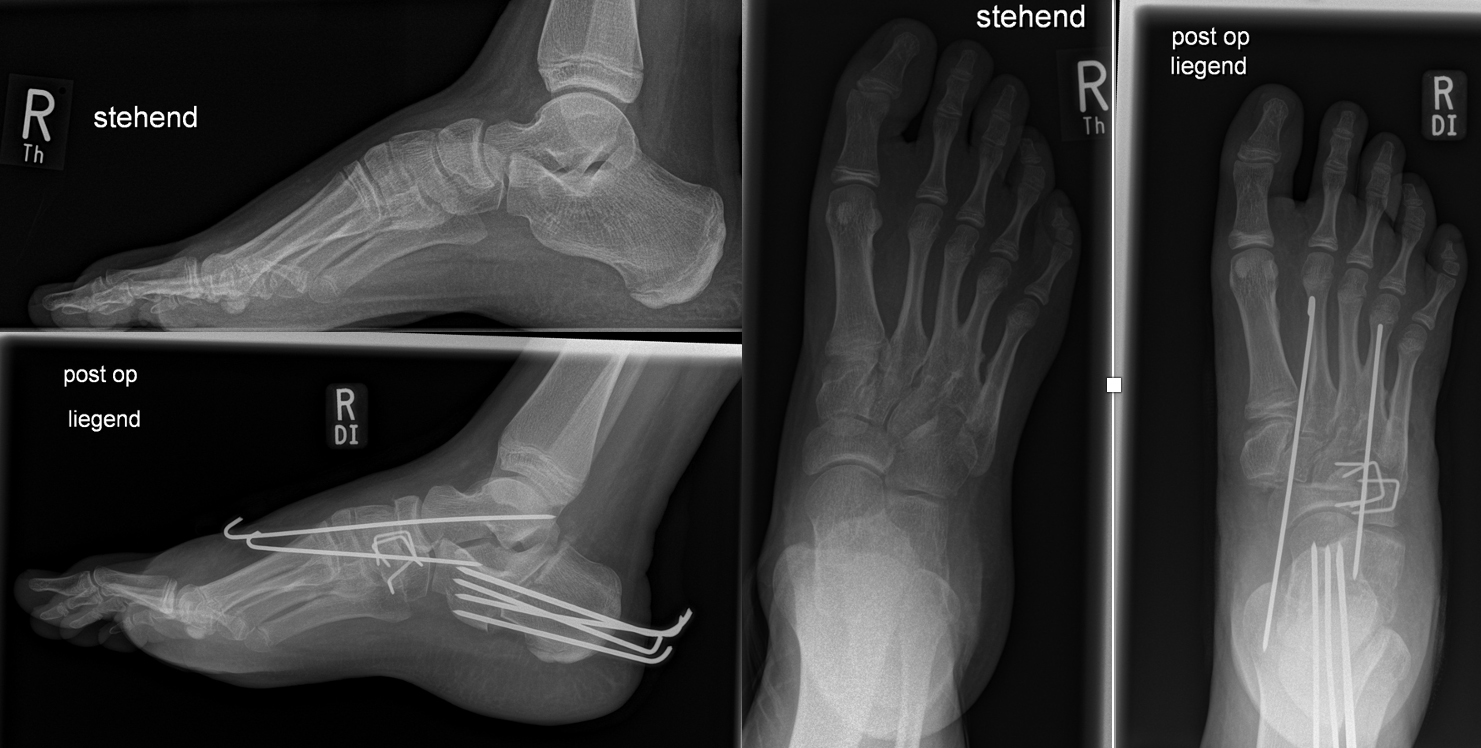

Calcaneus-Osteotomie

Die minimalinvasive Calcaneusverschiebeosteotomie bietet eindeutige Vorteile gegenüber dem offenen Verfahren, sodass wir bei Kindern und Jugendlichen nahezu keine offene Verschiebeosteotomie mehr durchführen. Am Calcaneus liegt die offene Wachstumsfuge dorsal. Bei der Durchführung müssen Schenkel der V-förmigen Osteotomie daher etwas steiler angelegt werden, in einem stumpfen Winkel (siehe Abb. 3 a-j). Für die Osteotomie liegen unsere Patienten auf dem Rücken und der BV wird für die exakte Seitaufnahme eingestellt. Der Fuß lagert auf einem hohen OP-Kissen und die Osteotomie kann bequem mit einem langen Kirschner-Draht und einem sterilen Stift angezeichnet werden (Abb. 15).

Damit lässt sich im Verlauf Röntgenstrahlung für die jungen Patienten vermeiden und die minimalinvasive Osteotomie kann sicher durchgeführt werden. Anschließend erfolgt die Verschiebung oder Impaktion. Ist ein Gleiten nach plantar oder cranial des distalen Fragmentes erwünscht, wird die Osteotomie schräg ohne V-Form entweder verlängernd oder verkürzend durchgeführt (Abb. 16).

Durch den knöchernen Defekt der Fräse gelingt die Verschiebung bei der minimalinvasiven Osteotomie im Fall von strukturell festen Klumpfüßen mit starkem Zug der verkürzten Achillessehne oder bei einer fixierenden spastischen Grunderkrankung einfacher gegenüber dem offen Verfahren. Ein weiteres Plus bei hyperaktiven Weichteilen ist die Vermeidung der ungewollten Cranialisierung des dorsalen Fragmentes durch die V-förmige Osteotomie (Abb. 16).

Die minimalinvasive Calcaneusverschiebeosoteotomie kommt somit in der Versorgung von kindlichen und jugendlichen Fußdeformitäten in einem weiten Erkrankungsspektrum zum Einsatz (Abb. 16):

- Plattfuß – Varisation

- Klumpfuß residual – Valgisation und ggfs. Cranialisation sowie Impaktion

- Klumpfuß überkorrigiert – Varisation und ggfs. Plantarisierung

- Hohlfuß – Cranialisation und ggf. Valgisation (alternativ minimalinvasive Austin-Osteotomie)

Abb. 16 a-f: Varisation einer valgischen Calcaneusstellung bei Knick-Senk-Fuß mit V-förmiger Osteotomie axiale Ansicht (a), seitliche Ansicht (b), d. p. Ansicht (c) und nach Entfernung der Drähte seitliche Ansicht (d), Caudalisierung des dorsalen Calcaneus bei iatrogenem Plattfuß nach Klumpfußüberkorrektur (e) und Cranialisierung beim Hohlfuß (f).